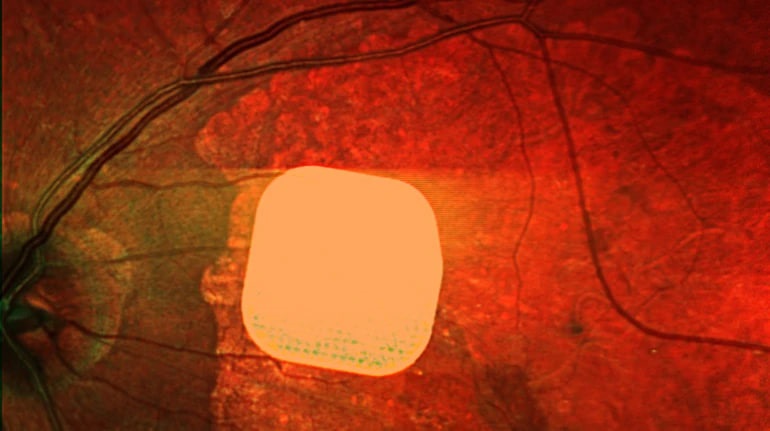

Британські лікарі успішно випробували новий електронний імплант Prima, який допомагає відновити зір пацієнтам із макулодистрофією – хворобою, що призводить до втрати зору у людей після 50 років. Цей мікрочип розміром 2×2 міліметри встановлюють під сітківку ока, а пацієнт користується спеціальними окулярами з камерою та комп’ютером для передачі зображення на мікрочип. Після операції 84% пацієнтів знову змогли розрізняти літери, цифри та слова. Ця технологія може значно покращити якість життя людей із важкими зоровими порушеннями, дозволяючи їм бачити і читати.